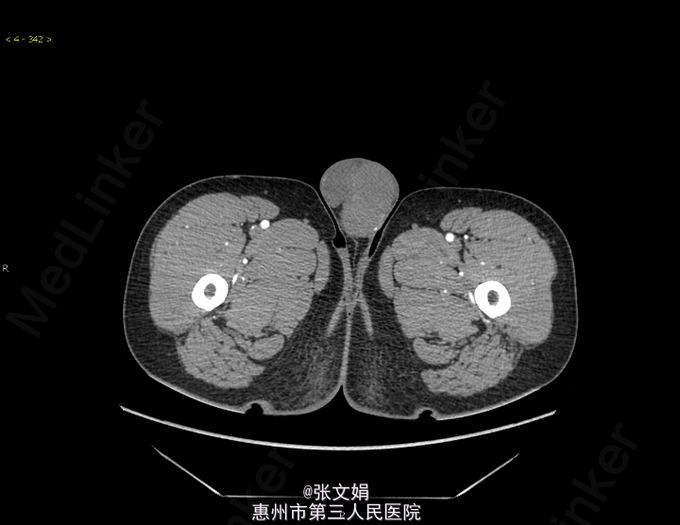

主诉:发现左侧阴囊肿大1月余 病史:患者无意中发现左侧阴囊肿大,无伴疼痛,发热,无腹痛腹胀,到我院门诊行CT检查,考虑左侧睾丸恶性肿瘤可能性大。

查体:左侧阴囊肿大,无疼痛。大小约为3cm*2cm大,类圆形,边缘稍规整。其余无特殊。 辅查:门诊CT检查,考虑左侧睾丸恶性肿瘤可能性大。 PET示:左侧睾丸恶性肿瘤(生殖细胞瘤)可能性,右侧斜裂小结节,考虑肉芽肿。 术后病理提示:(左侧睾丸)精原细胞瘤。

诊断:左侧睾丸精原细胞瘤 处理:行左侧睾丸根治性切除术